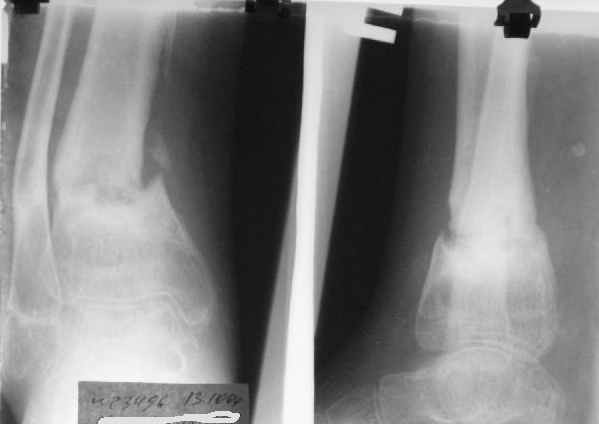

Уважаемые коллеги!Поступила пациентка 40лет, псевдоартроз Н/3 большеберцовой кости, оперирована 1,5-а года назад по поводу перелома ПИЛОНА в Австрии, травма горнолыжная.

после остеосиннтеза |  05.07.04 |  12.04.05 | Пластина удалена через 4-е месяца (миграция винтов), полимерная повязка на 2-а мес. Беспокоит деформация голени,укорочение 1-1,5см, боли незначительные, движения в г/стопном суставе в полном объёме, ходит с полной нагрузкой на ногу, подвижность в переломе не определяется. Одномоментное исправление деформации, костная пластика (chronOS)+ пластина? Аппаратная коррекция, затем пластина? Аппарат? Прошу Ваших советов. С Уважением А.Миронов